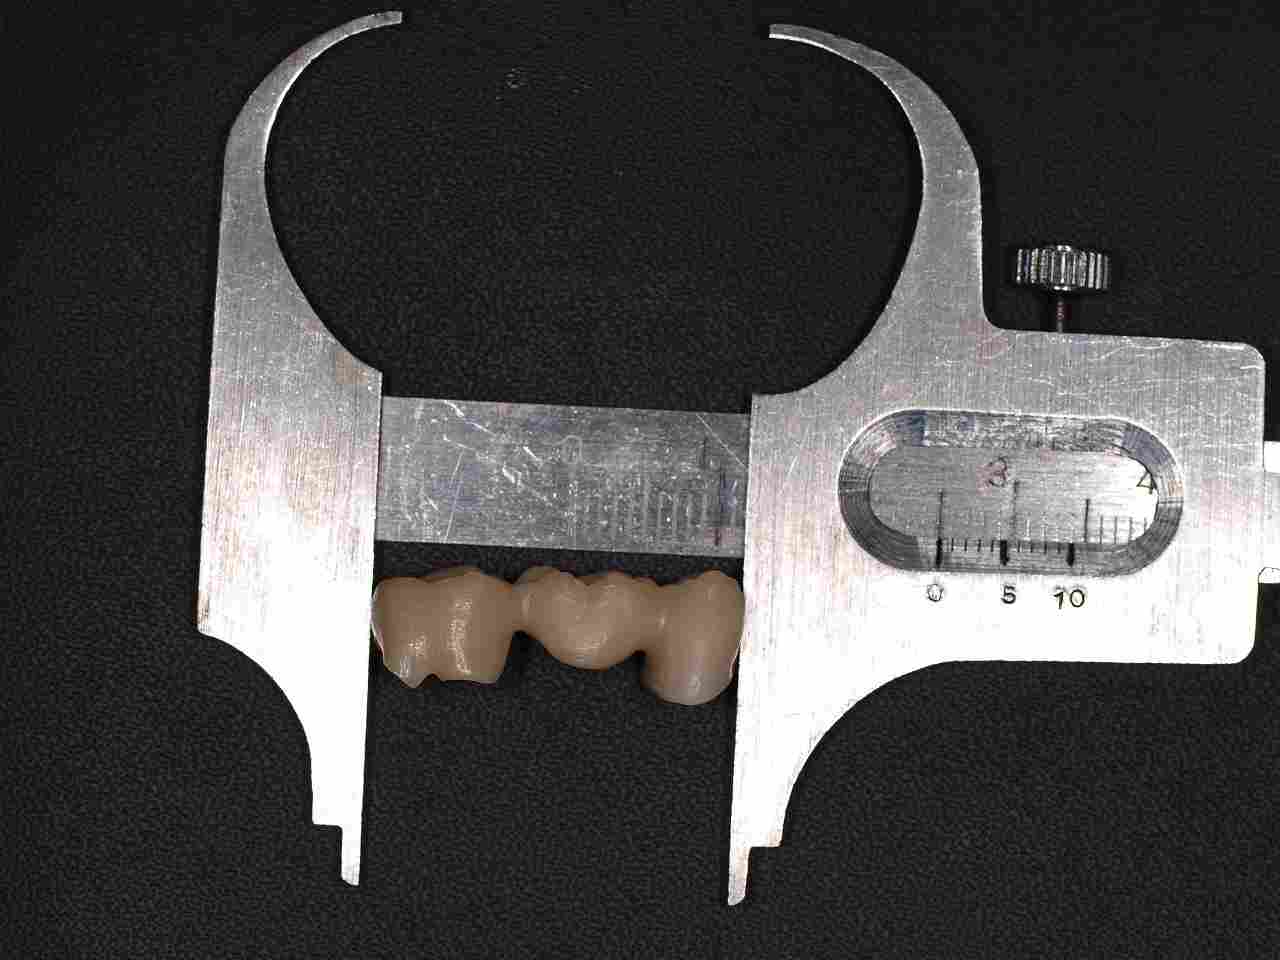

ジルコニアフレームを使用したジルコニアブリッジも6歯程度まででそれ以上になると従来通りのメタルボンドに切り替えるようにしています。 ワンピースではフレイムの適合、制度が落ちる為郎着作業が必要となりジルコニアは蝋着ができないことが理由に挙げられます。|お知らせ |広島市安佐南区の歯科医院

ジルコニアフレームを使用したジルコニアブリッジも6歯程度まででそれ以上になると従来通りのメタルボンドに切り替えるようにしています。 ワンピースではフレイムの適合、制度が落ちる為郎着作業が必要となりジルコニアは蝋着ができないことが理由に挙げられます。

ジルコニアフレームを使用したジルコニアブリッジも6歯程度まででそれ以上になると従来通りのメタルボンドに切り替えるようにしています。 ワンピースではフレイムの適合、制度が落ちる為郎着作業が必要となりジルコニアは蝋着ができないことが理由に挙げられます。